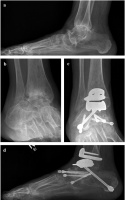

Abbildung 1: Patientin mit Panarthrose des Rückfußes auf Boden einer primär chronischen Polyarthritis präoperativ (a, b) sowie nach Implantation einer HINTEGRA-Sprunggelenksprothese und simultaner Rückfußarthrodese (c, d)